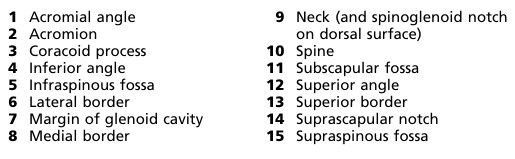

Mock 3a Shoulder and (3b hip)